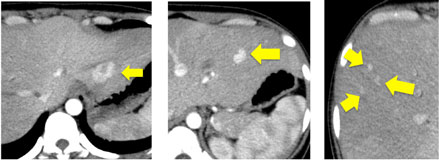

脂肪肝とは?CT,MRI画像診断のポイントは。